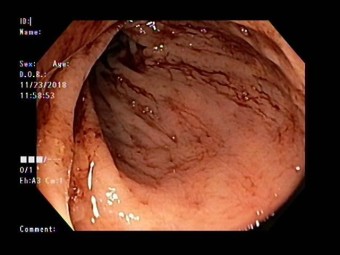

대장내시경 검사 방법

대장내시경은 대장암을 90% 이상 선별하는 방법으로 알려져 있어요. 대장 내시경 검사 시 실제로 암이 발견되면 정밀 검사를 받아야 해요. 먼저 정확한 진단을 받기 위하는 것은 대장내시경 전 식품 유의사항을 정확히 지키는게 중요해요. 식품 유의사항을 잘 지켰다면 병원을 방문하여 검사를 받게 되는데, 검사 시 편한 옷을 갈아입고, 왼쪽 방향으로 옆으로 누운 다음 무릎을 구부린 자세를 취해요. 그다음은 수면 내시경으로 진행한다면 진정제를 투입하면 잠이 들면 항문을 통해 의료 내시경을 삽입하여 검사를 하게 되어요. 비수면의 경우 내시경 삽입 시 강력한 힘이나 말을 하게 되면 삽입이 어려울 수 있기 때문에 긴장을 가능한 한 풀고 진행하게 되어요. 검사 시간은 환자에 따라 조금씩 다르지만 20-30분 정도 소요된다고 해요.